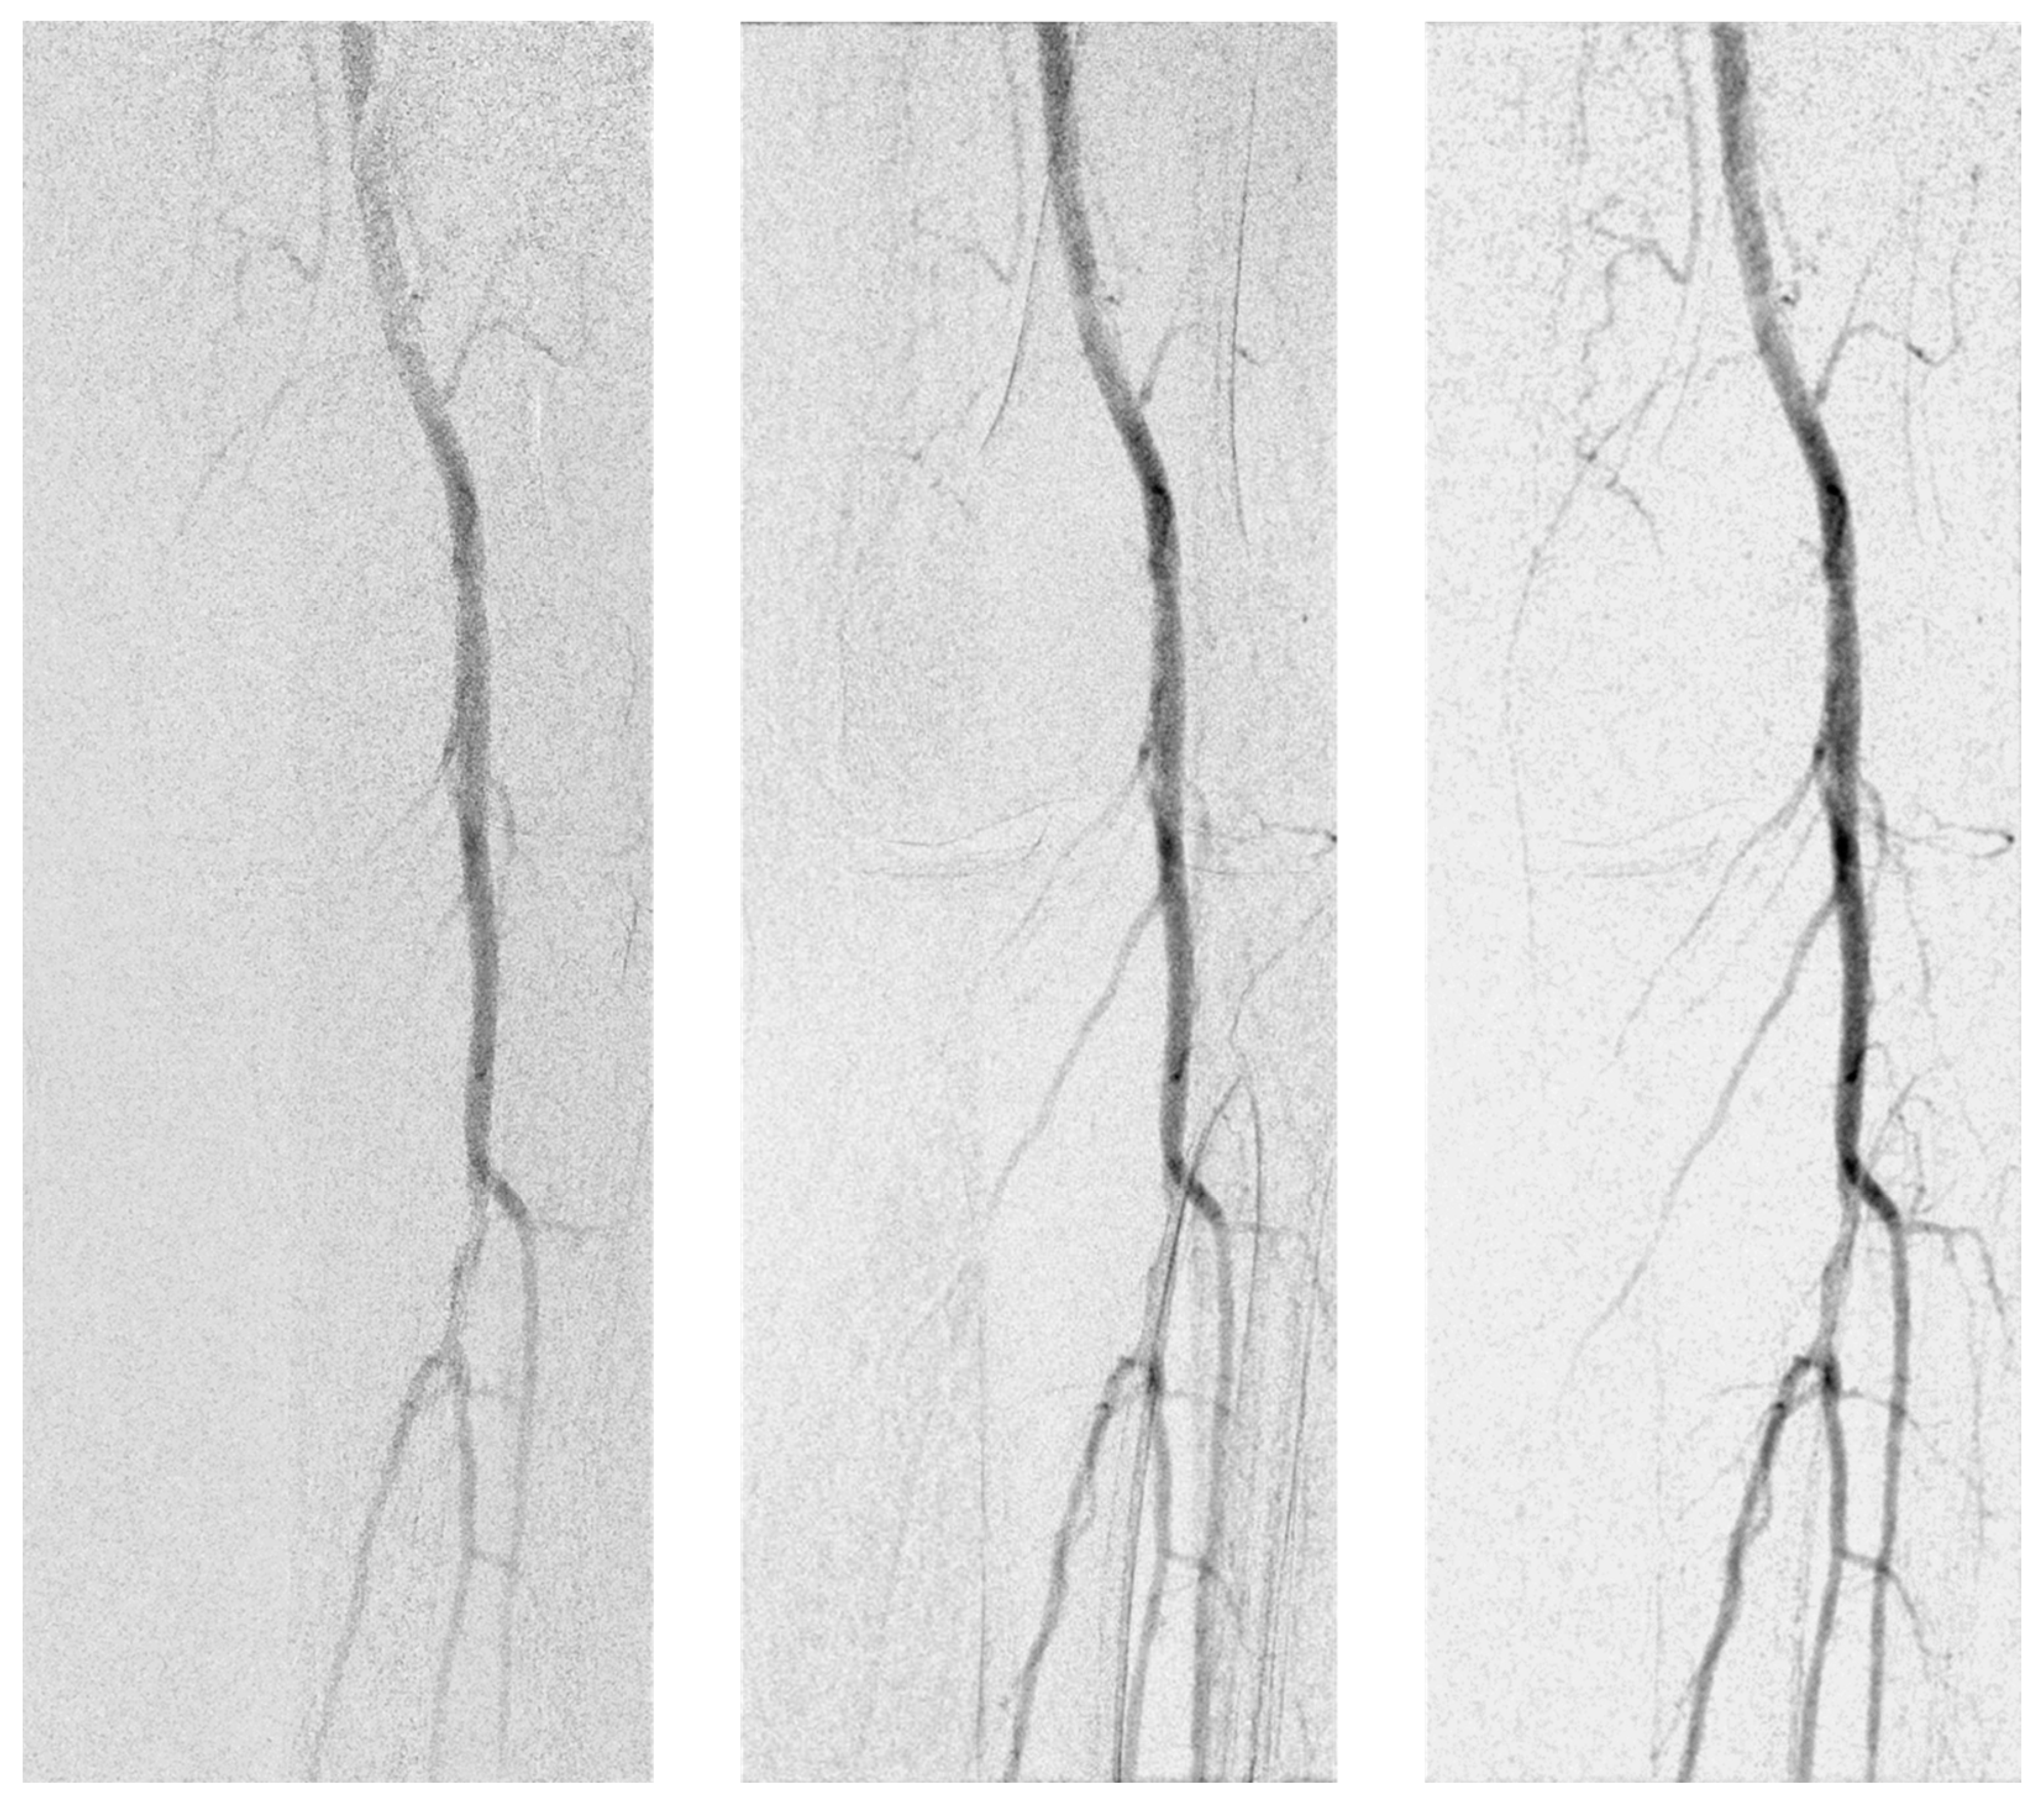

2.4. Image Processing

2.5. Visual Evaluation

3.3. Visual Evaluation